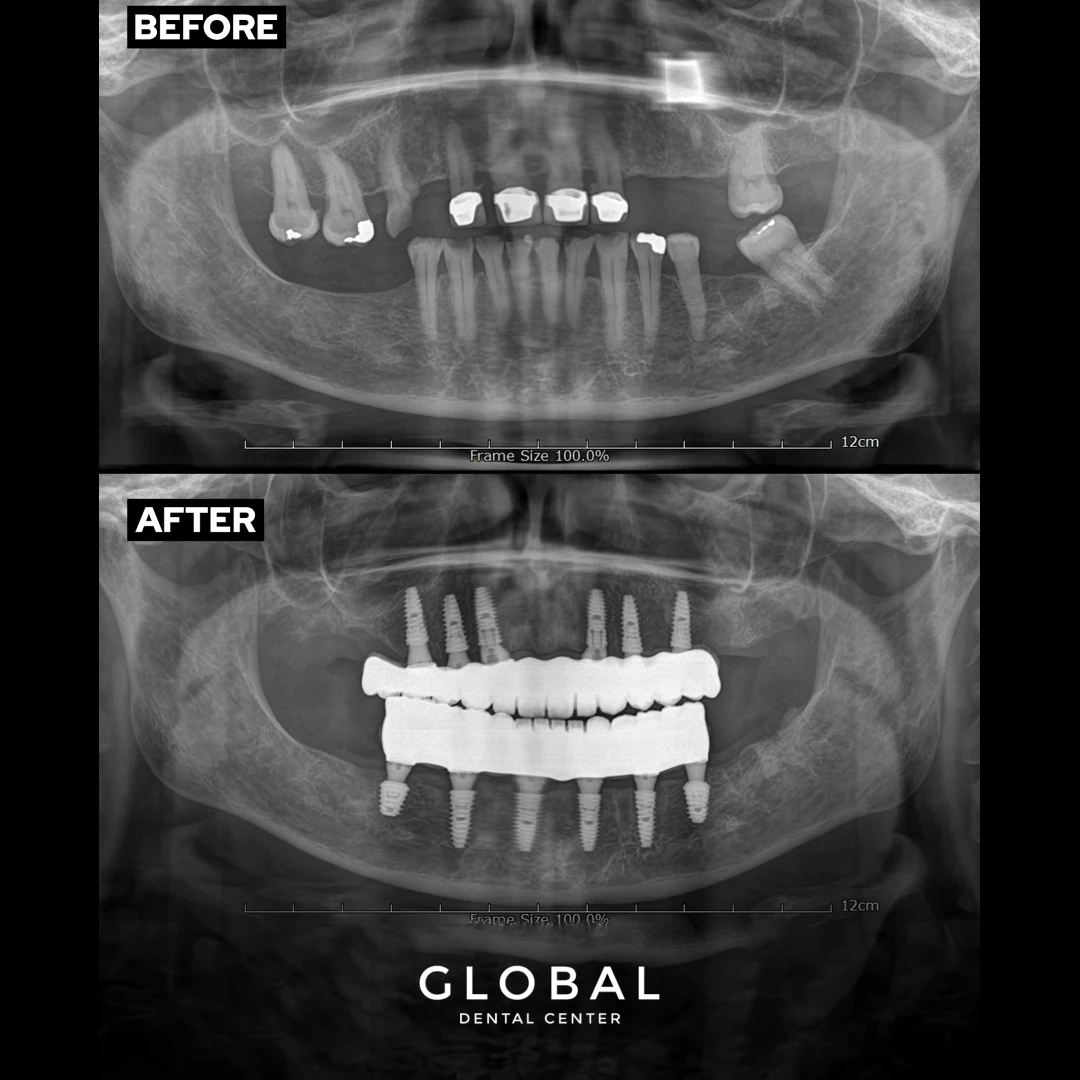

Unter All-On-6 versteht man eine Art der Implantationstechnik, bei der alle Zähne des Ober- oder Unterkiefers mit nur 6 Zahnschrauben ersetzt werden können. All-On-6-Zahnimplantate verhelfen Patienten, die die meisten ihrer Zähne verloren haben oder ein Zahntrauma erlitten haben, bei dem viele Zähne abgebrochen oder ungesund sind, zu einem schönen, natürlich aussehenden Lächeln.

Im Vergleich zu herkömmlichen Zahnimplantaten ist die All-On-6-Technik weniger invasiv, da weniger Ankerschrauben erforderlich sind. Wenn ein Patient beispielsweise 10 Zähne mit herkömmlichen Zahnimplantaten ersetzen soll, müssen 10 Ankerschrauben eingesetzt werden. Mit All-On-6-Technik können alle Zähne des Ober- oder Unterkiefers mit nur 6 Ankerschrauben ersetzt werden, was zu einer kürzeren Einheilzeit führt.

Da wir Ihre All-On-6-Implantation in Antalya im Voraus planen, kennen wir Ihre speziellen Bedürfnisse genau und gehen mit größter Sorgfalt vor. Bevor wir Ihre All-On-6-Zahnimplantate einsetzen, entfernen wir alle noch vorhandenen Zähne. Dr. Kartöz setzt dann vorsichtig 6 Ankerschrauben in den Zahnfleischrand ein, die als sicheres Fundament für Ihre neuen Zähne dienen werden. Am Tag Ihres Klinikbesuchs wird ein Satz provisorischer Zähne eingesetzt, während Sie sich von Ihrem All-On-6-Zahnimplantat erholen.

Es werden provisorische Zähne eingesetzt, damit Sie ohne Schwierigkeiten essen und sprechen können, während Ihre All-On-6-Zahnimplantate eine Phase der Osseointegration durchlaufen. Dies ist der Zeitpunkt, an dem die Ankerschrauben Ihres Zahnimplantats beginnen, sich mit Ihrem Zahnfleisch und Kieferknochen zu verwachsen, um eine dauerhafte Grundlage für Ihr neues Gebiss zu schaffen. Die bei All-On-6-Zahnimplantaten verwendeten Ankerschrauben funktionieren ähnlich wie die Wurzeln Ihrer natürlichen Zähne und sorgen dafür, dass Ihre Implantate sicher im Kieferknochen verankert sind. Die Osseointegration kann 3-5 Monate dauern. Im Anschluss daran kommen Sie zu einer Nachuntersuchung in unsere Zahnklinik, wo ein Satz bleibender Zähne eingesetzt wird. Bei Global Dental Center garantieren wir die Lebensdauer Ihrer All-On-6-Zahnimplantate.